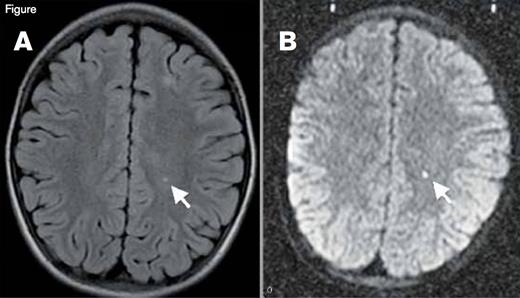

Silent Cerebral Infarction (SCI). A small stroke is visualized here in T2-weighted (panel A) and diffusion-weighted magnetic resonance images (panel B) in a patient with sickle cell disease. Given the restricted diffusion (panel B), this stroke was imaged in the acute phase (onset in the past 10 to 14 days). This patient with incidentally discovered acute silent cerebral ischemia was asymptomatic, had a normal neurologic examination, was in his baseline state (“steady-state”), and was undergoing a screening MRI for a clinical trial. The motor strip was not affected by this stroke, so it is classified as “silent” (an SCI), but a stroke is a stroke, and the brain is more than a motor strip.

As hematologists we provide much of the medical care for patients with sickle cell disease (SCD), so we need to remain cognizant that SCD is a truly multisystem disease that affects most tissues and organs beyond the blood and bone marrow. For example, the brain is at ongoing threat of ischemic injury in SCD.1 The risk of overt stroke for children with SCD (without primary stroke prophylaxis) is more than 200-fold higher than the general population, and the burden of stroke may be even higher in adults with SCD.2 As if overt stroke were not worrisome enough, a far more common form of brain injury is silent cerebral infarction (SCI). SCI refers to generally small, permanent brain lesions that do not produce localizing neurologic signs (Figure). The lack of localizing signs should not reassure us, however, because the brain is more than a motor strip. Indeed, SCI is a misnomer because these smaller strokes are often not “silent.” SCI is a morbid condition associated with neurocognitive impairment, poor academic performance, neurologic soft signs, and an increased risk of subsequent overt stroke. SCI can occur as early as the first year of life, and its prevalence increases with age. Approximately 40 percent of adolescents with SCD have SCI, and adults probably continue to acquire new or enlarged SCI lesions.3,4 Despite the high frequency and morbidity of SCI, we have had no randomized clinical trials (with SCI as the primary outcome) to inform medical therapy for patients with SCI, until now.